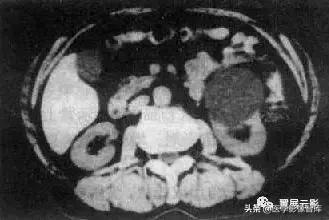

肾癌

肾癌最常见的肾恶性肿瘤,主要发生在中老年,男多于女,临床典型表现为无痛性血尿,肾癌可有假性包膜,血供丰富,大体病理切面为实性,常有坏死,出血和囊变,少数有钙化,晚期肾癌发生肾周脂肪囊和肾周各间隙的侵犯,淋巴结转移和肾静脉,下腔静脉瘤栓。

MRI表现:T1WI肾癌一般呈低信号,等信号时容易漏诊,此时仅见局部皮髓质交界的消失,冠状面对于肾脏轮廓的显示更清晰;T2WI肾癌一般为不均匀较高信号,但有时为等信号或较低信号,注意观察肾癌的假包膜,T1WI和T2WI均为低信号,增强扫描为必须检查项目,可有不同程度和形式的增强,对于肾盂肾盏受压和肾周肾窦脂肪受侵,淋巴结转移或肾静脉,下腔静脉瘤栓等情况也应观察描述,并进行肿瘤的分期。